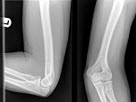

50、单项选择题

女,根据其正常肘关节影像图像,判断其最可能的年龄()

A.17岁左右

B.27岁左右

C.67岁左右

D.37岁左右

E.57岁左右